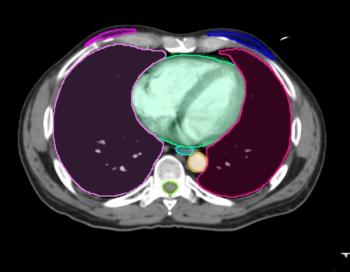

Updates to Contour ProtegeAI 4.0 reportedly include enhanced algorithms for radiation oncology segmentation and molecular radiotherapy.